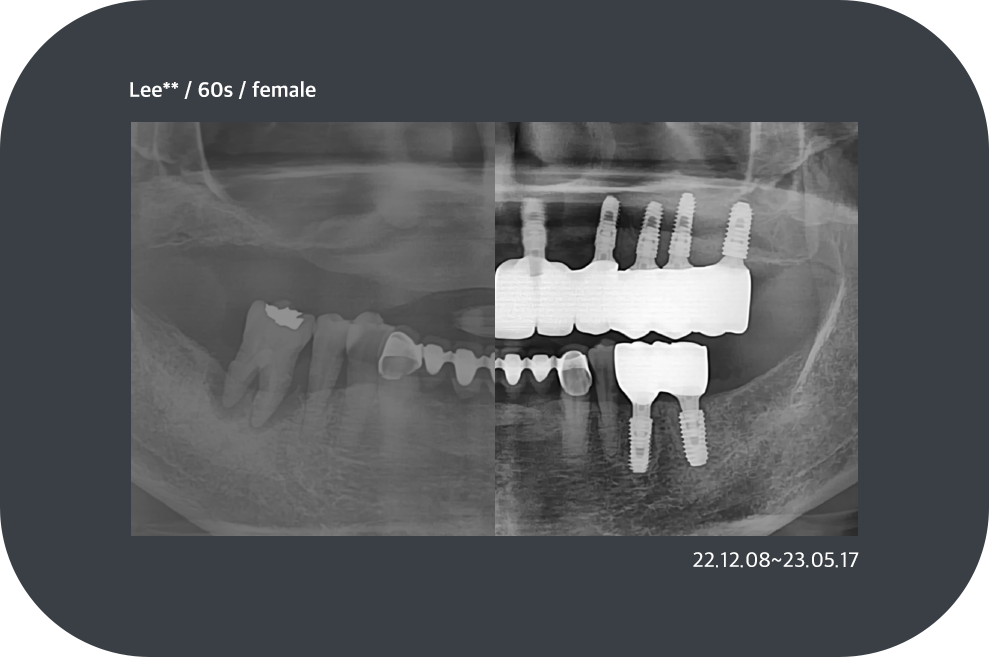

치료사례

임플란트 치료사례

*모든 증례 사진은 의료법 제23조, 제56조에 의거하여, 당사자의 동의하에 게시하였습니다.

*치료 사진은 모두 본원에서 치료한 환자분의 사진입니다.

*치료 사진은 모두 동일인의 사진이며, 동일조건에서 촬영하였습니다.

*개인의 차이에 따라 시술 및 수술 후 부작용이 발생할 수 있으며, 의료진과 충분한 상담을 받으시기 바랍니다.